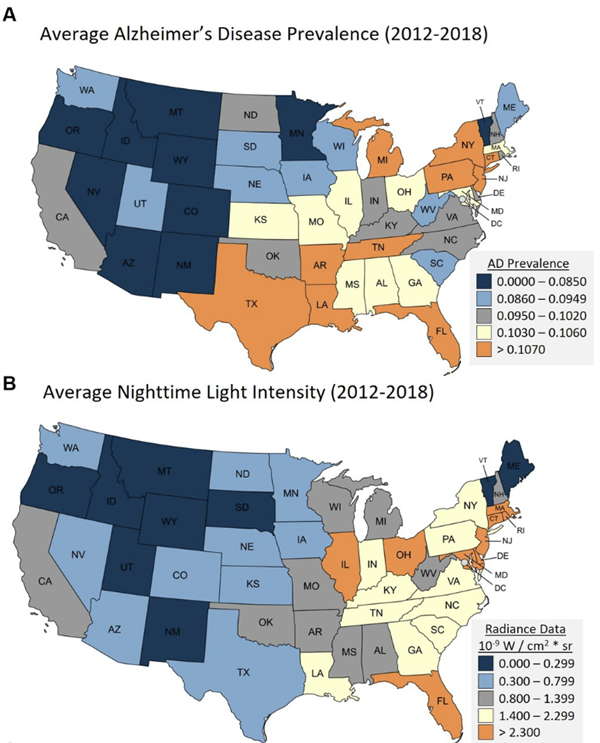

睡前一个小动作 居然可能让你远离老年痴呆